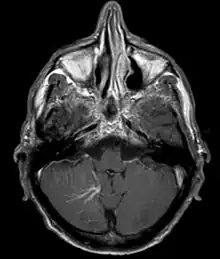

| Developmental venous anomaly in the cerebellum seen on axial contrast-enhanced T1 weighted MRI | |

A developmental venous anomaly (DVA, formerly known as venous angioma) is a congenital variant of the cerebral venous drainage. On imaging it is seen as a number of small deep parenchymal veins converging toward a larger collecting vein.

DVA can be characterized by the caput medusae sign of veins, which drains into a larger vein. The drains will either drain into a dural venous sinus or into a deep ependymal vein. It appears to look like a palm tree.[1]